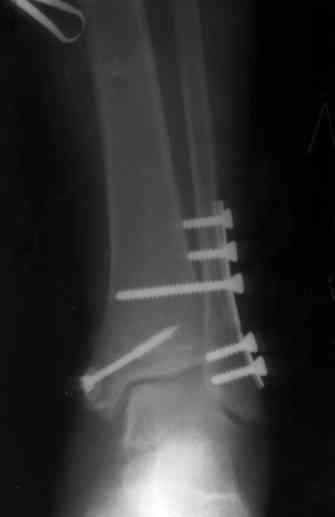

Пока я был в интернатуре, предпочитали осуществлять стабильный остеосинтез с ранней функцией. См. приложения и полнотекстный вариант

статьи.